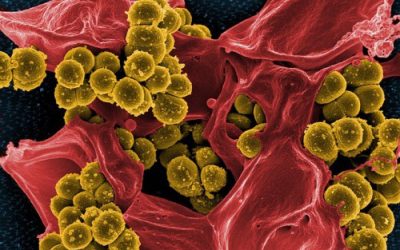

Prescrire : la liste noire des 91 médicaments à éviter

Depuis cinq ans, la revue Prescrire publie une liste noire de médicaments mis sur le marché qu’il est préférable d’éviter, car considérés comme inutiles, voire dangereux. Le nouveau recensement vient de paraître.